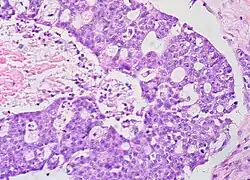

Histopathology

In case an ovarian cyst is surgically removed, a more definite diagnosis can be made by histopathology:

| Type | Subtype | Typical microscopy findings | Image |

|---|---|---|---|

| Functional cyst | Follicular cyst |

|

| Corpus luteum cyst |

| |

| Cystadenoma | Serous cystadenoma | Cyst lining consisting of a simple epithelium, whose cells may be either:[26]

| Mucinous cystadenoma | Lined by a mucinous epithelium |

| Dermoid cyst | Well-differentiated components from at least two, and usually three,[11] germ layers (ectoderm, mesoderm and/or endoderm).[27] |

| Endometriosis | At least two of the following three criteria:[28]

| Borderline tumor | Atypical epithelial proliferation without stromal invasion.[29] |

| Ovarian cancer | Many different types, but generally severe dysplasia/atypia and invasion. |

| Simple squamous cyst | Simple squamous epithelium and not conforming to diagnoses above (a diagnosis of exclusion) |